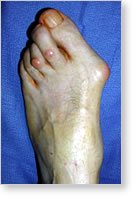

Arthritis can have significant effects on the feet and the ankle. These range

from swelling of the toe joints to severe destruction of the joints of the foot

and the ankle. The process of joint inflammation begins with an inflammation of

the lining of the joints called the capsule. As the capsule becomes inflamed,

the joint fills with fluid and becomes painful. The cartilage lining of the

joint may wear out.

The joint space becomes narrow and bone begins to rub on bone, leading to

painful arthritis. In addition, deformities may occur as a result of loosening

of the ligaments and capsule lining of the joint. If the housing of the joint

(the capsule) loosens up significantly, the joints (particularly in front of the

foot) may dislocate. This can cause painful swelling on the bottom of the ball

of the foot that can make walking terribly uncomfortable. In addition to the

dislocation of the joints, the big toe begins to deviate and bunions may form on

the inside of the big toe.